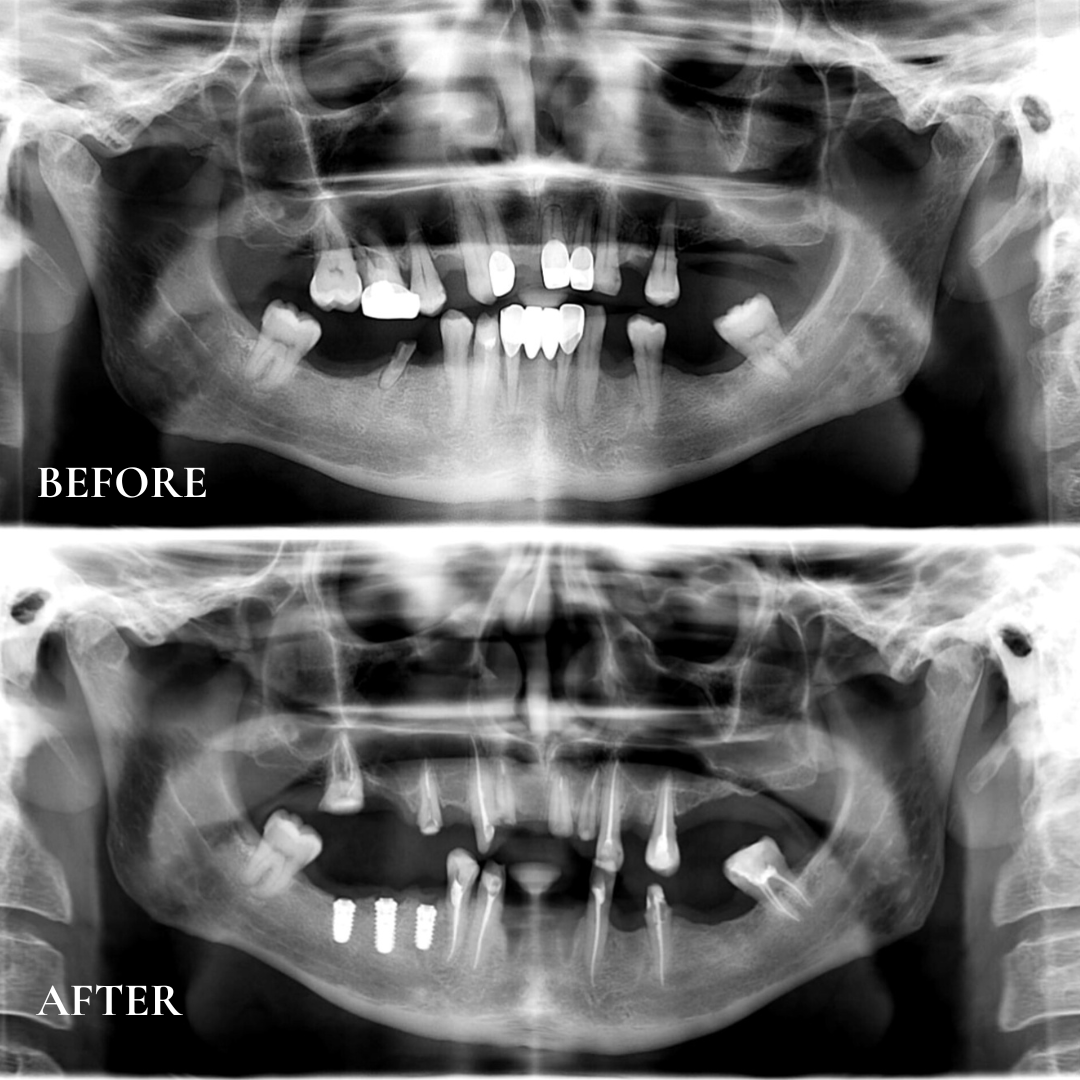

Декілька місяців тому, на клінічній базі `медичного центру «Усмішка», надали стоматологічну допомогу Захиснику України Гапченку Ігорю Володимировичу, який отримав поранення правого плеча та м’яких тканин лівої стопи, при виконанні службових обов’язків, пов’язаних з захистом Батьківщини, в результаті обстрілу позицій противником на Донецькому напрямку. Військовослужбовець звернувся до благодійної організації «Зуб за Зуб» з питанням відновленням повноцінної функції жування.

Проведено огляд кваліфікованими лікарями та додаткові методи обстеження (комп’ютерна томографія, ортопантомограма та 3D сканування ротової порожнини), складено протокол лікування та узгоджено з пацієнтом.

2. Видалення: 42, 46, 32, 24, 16;

8. Перший етап встановлення двоетапового імплантата Bredent: 45, 46, 47;